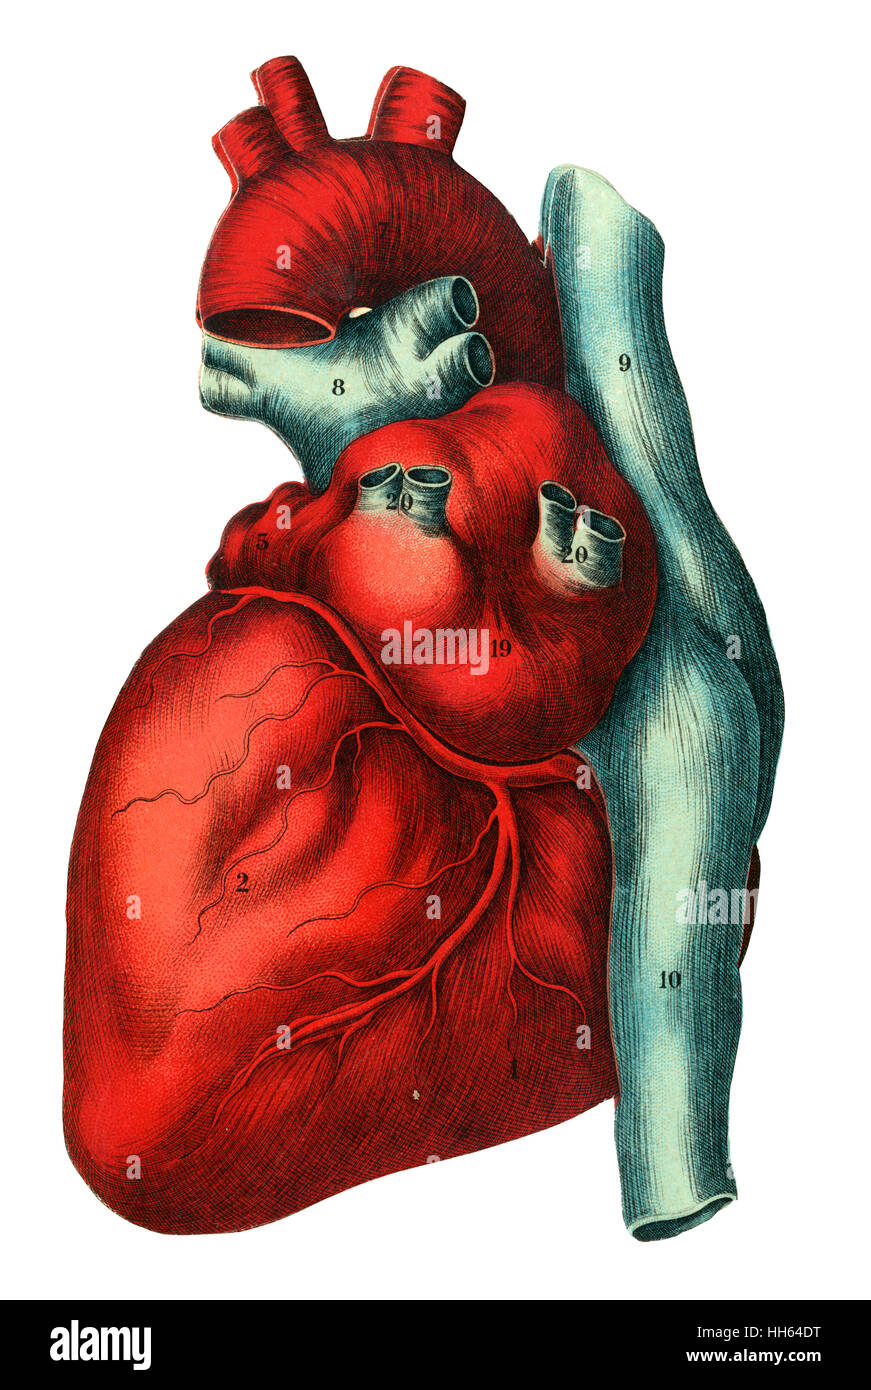

Illustration of a human heart - top of a layered anatomical fold-out in a medical book. Stock Photohttps://www.alamy.com/image-license-details/?v=1https://www.alamy.com/stock-photo-illustration-of-a-human-heart-top-of-a-layered-anatomical-fold-out-131056964.html

Illustration of a human heart - top of a layered anatomical fold-out in a medical book. Stock Photohttps://www.alamy.com/image-license-details/?v=1https://www.alamy.com/stock-photo-illustration-of-a-human-heart-top-of-a-layered-anatomical-fold-out-131056964.htmlRMHH64DT–Illustration of a human heart - top of a layered anatomical fold-out in a medical book.